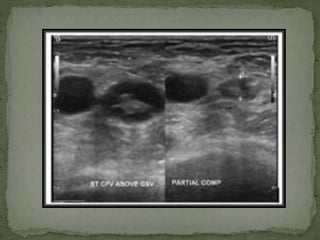

1. Grey Scale – drect visualization of thrombus with

lack of compressibilty. Some acute thrombus

might be anechoic.

 Therefore , lack of complete venous compression is

hallmark finding of DVT.

2. Color doppler- Persistent filling defect with thrombus

in colour column of vessel lumen or complete

absence of flow.